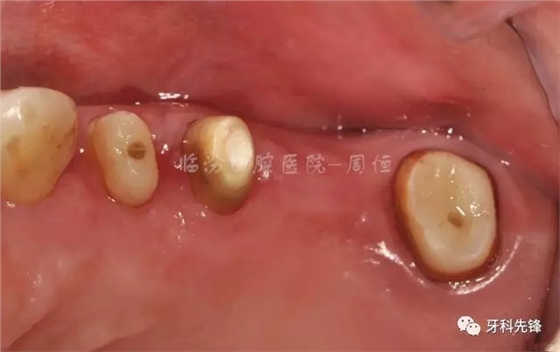

圖9去除腐質(zhì)口內(nèi)照

640.webp (13).jpg

圖10冠延長(zhǎng)術(shù)后照

640.webp (14).jpg

圖11術(shù)后一個(gè)月纖維樁修復(fù) 牙體預(yù)備

640.webp (15).jpg